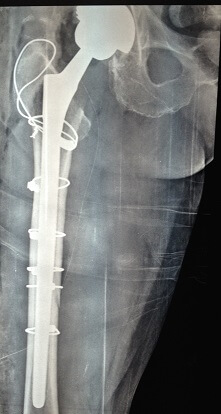

Εικόνα 3: Αναθεώρηση ολικής αρθροπλαστικής